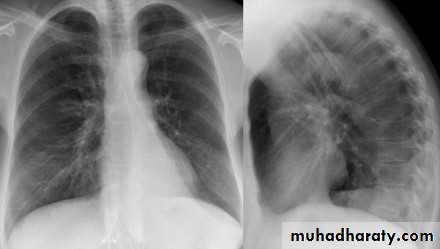

CXR of adult male, PA and lateral views show:

Well defined rounded cavitatory lesion in the middle zone of the right lung with air fluid level insideLung abscess

Well defined rounded lesion in the middle zone of the right lung with air fluid level inside